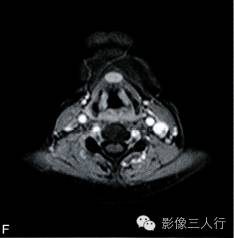

A~B. T1WI横断位;C~D. T2WI压脂横断位; E~F. T1WI压脂增强横断位;G. HE×100

卵圆形结节影位于舌骨中线,T1WI呈低信号,T2WI压脂序列呈稍高信号,信号均匀。增强后明显均匀强化,约1.3cm×0.8cm×1.6cm,其右前方下颌间隙内亦见一小结节,约0.7cm×0.4cm×0.5cm,信号特点与舌骨中线结节大致相同。颈部软组织结构清楚,未见异常信号影,气管居中,无受压或移位。颈部MRI平扫两侧见正常甲状腺组织,信号欠均匀(图A~F)。